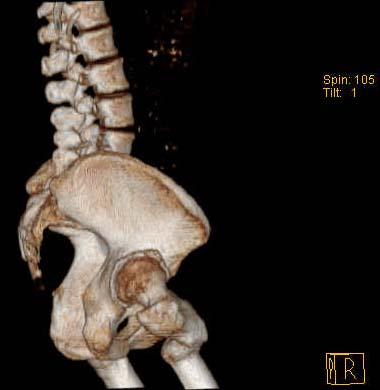

Уважаемые коллеги!Женщина, 35 летВ прошлом по поводу врожденного вывиха бедра перенесла операцию остеотомии по Шанцу

с удлинением правой ноги за счет бедра на уровне диафиза. В последнее время прогрессируют боли в правом тазобедренном суставе, порочное положение правой ноги, затруднена ходьба.Вопросы:1) Целесообразно ли эндопротезирование правого тазобедренного сустава?2) Целесообразный ли следующие действия: канал бедренной кости предполагаем вскрыть для введения ножки протеза на высоте угловой деформации, предполагаем низведение большого вертела с мышцами; протез будет подобран индивидуально, предполагается умеренная версия?В приложении рентгенограммы и трехмерная КТ.В цветном и более качественном варианте КТ размещена здесь